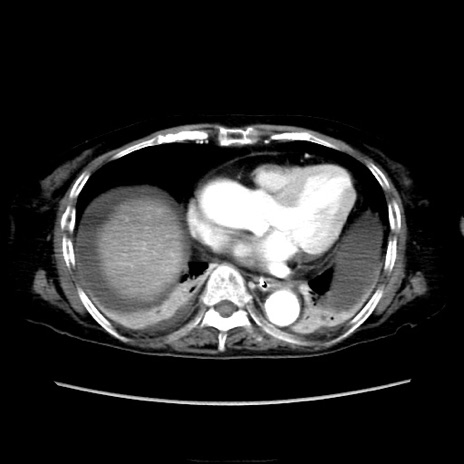

症例40(横断像)

【症例】90歳代女性

【主訴】腹痛・嘔吐

【現病歴】 食欲低下、嘔吐があり昨日他院受診。肺炎と診断され入院となる。入院後より腹部全体に圧痛あり。胃管留置され経過みていたが、症状持続するため、

当院転院となる。

【既往歴】胸椎圧迫骨折、胆石症

【身体所見】腹部:中央に激痛あり、圧痛あり、反跳痛不明

【データ】WBC 17100、CRP 18.82

横断像